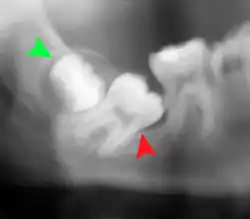

Las muelas del juicio impactadas se clasifican según la dirección y la profundidad de la impactación, la cantidad de espacio disponible para la erupción dental y la cantidad de tejido blando o hueso (o ambos) que las recubre. La estructura de clasificación ayuda a los clínicos a estimar los riesgos de impactación, infecciones y complicaciones asociadas a la extracción de las muelas del juicio.[6] Las muelas del juicio también se clasifican por la presencia (o ausencia) de síntomas y enfermedad.[7]

Las muelas del juicio impactadas suelen describirse por la dirección de su impactación (la inclinación hacia delante o mesioangular es la más común), la profundidad de la impactación y la edad del paciente, así como otros factores como la infección preexistente o la presencia de patología (quistes, tumores u otras enfermedades):[5] Cada uno de estos factores se utiliza para predecir la dificultad (y la tasa de complicaciones) al extraer un diente impactado, siendo la edad el factor predictivo más fiable,[8] que la orientación de la impactación.[9]

La coronectomía es un procedimiento en el que se extrae la corona de la muela del juicio impactada, pero las raíces se dejan intencionadamente en su sitio. Está indicada cuando no hay enfermedad de la pulpa dental ni infección alrededor de la corona del diente, y existe un alto riesgo de lesión del nervio alveolar inferior.[32]